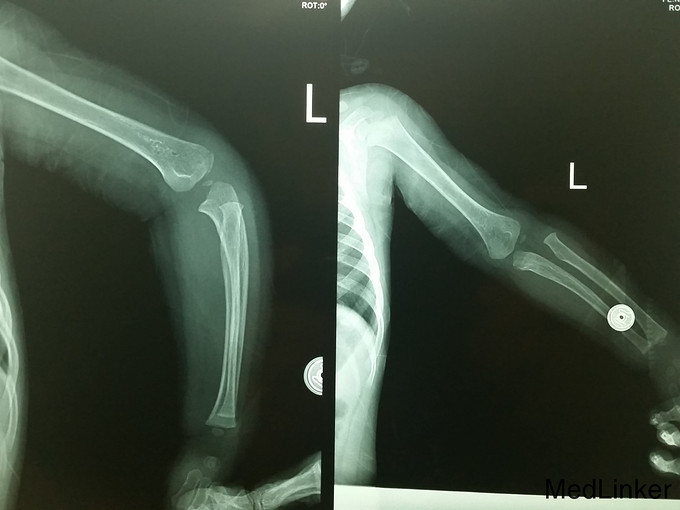

复杂骨折

骨折

男,1岁10月,约1米高台跳下时伤及左侧肘部,肿胀活动受限

左上肢石膏长臂石膏后托固定,左手活动可

请教各位诊断及治疗方案